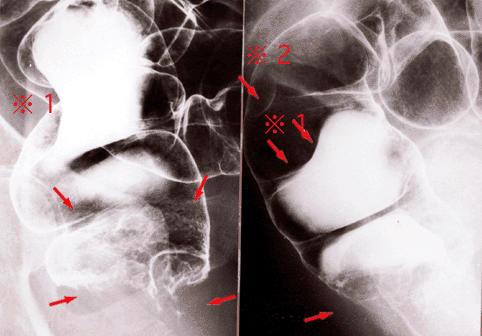

Rectal malignant melanoma with regional lymph node metastasis demonstrated by a double contrast barium enema.

Tokyo Pref., Cooperative study between National Cancer Center and Kyushu Cancer Center

Malignant melanoma/

Large intestine(Colon)/Rectum

X-ray

40 -

muscularis propria